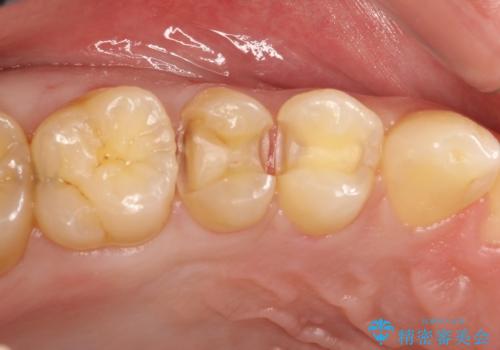

- 時々冷たいものがしみるといらした患者様です。

歯科医院に行くこと自体が久しぶりだったようで、口腔内にはたくさん虫歯がありました。

小さな虫歯に関しては保険内の白い詰め物にて、虫歯の大きい箇所はセラミックインレーにて修復しました。